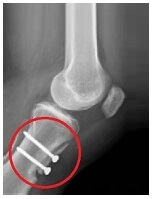

If there is abnormal bony alignment at the knee, then realignment surgery may be performed. The tibial tubercle is the bony lump on the front of the tibia (shin bone) just below the knee where the patella tendon attaches.

The tubercle is lifted and repositioned medially then fixed in place with pins or screws. This shifts the pull on the kneecap inwards, which reduces the lateral pull on the kneecap.

Rehab following surgery will focus on regaining full movement, strength and stability at the knee and will be similar to the rehabilitation programme described above.